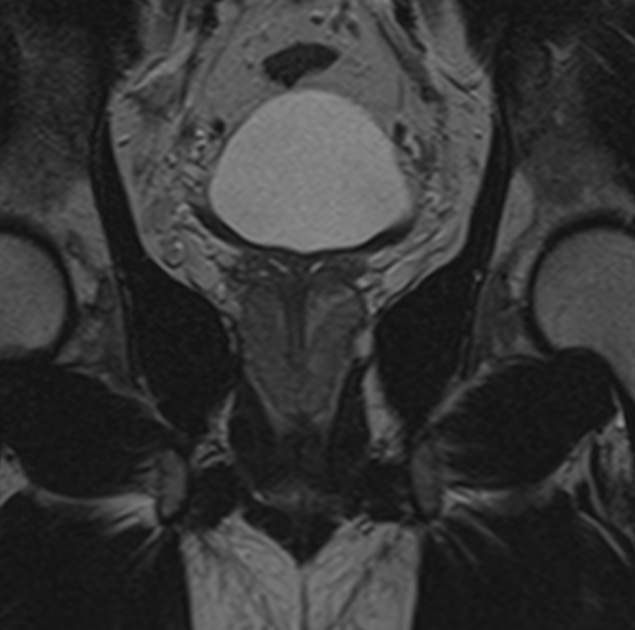

Простата расположена в труднодоступной для диагностики анатомической области, однако метод магнитно-резонансной томографии позволяет детально изучить структуру органа и окружающих ее тканей, включая семенные пузырьки (секреторные органы, вырабатывающие жидкую часть семенной жидкости) и семявыносящие протоки.

В клинике «Доступная медицина» диагностика заболеваний предстательной железы на экспертном уровне выполняется при помощи современного высокопольного магнитно-резонансного томографа TOSHIBA VANTAGE TITAN 1,5 Тесла. Аппарат производит сканирование в виде послойных тонких срезов с шагом от 1 мм и преобразует их при помощи новейших цифровых программ в изображения трехмерного формата. Методика позволяет получить максимально полную картину о состоянии структуры простаты и окружающих тканей и поставить точный диагноз.